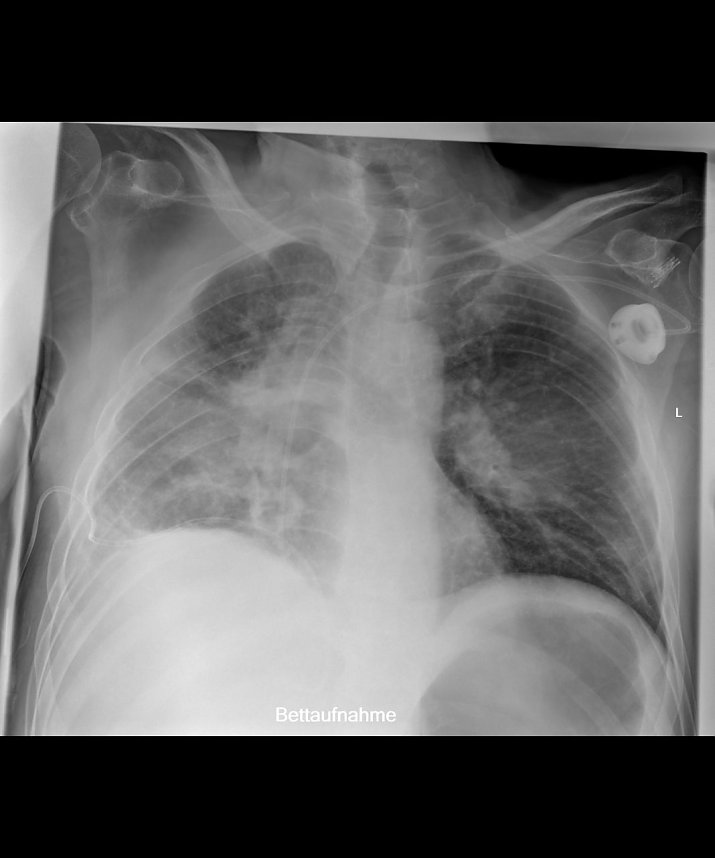

Liegendaufnahme mit SkyFlow Technologie (Foto: SHK)